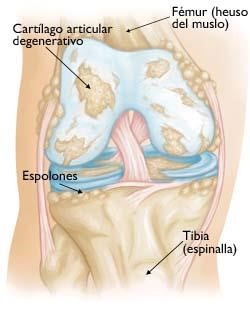

Los estudios previos para el diagnostico de una artrosis de rodilla son principalmente un examen clínico del médico y las radiografías. El examen medico habitualmente confirma dolor en la parte medial, anterior y lateral de rodilla, rigidez con reducción en el rango de movimiento, crepitación o roce con el movimiento de la rodilla y cojera durante la marcha. En la radiografía típicamente se observa los cambios en la forma del hueso y cartílago como la pérdida de grosor, deformación y endurecimiento. Ocasionalmente para confirmar el diagnóstico de la patología de un compartimiento o de una fase muy inicial, se puede usar otras pruebas de imagen como la resonancia magnética, tomografía computarizada (TC) o gammagrafía ósea que valora mejor las partes blandas alrededor de la articulación.